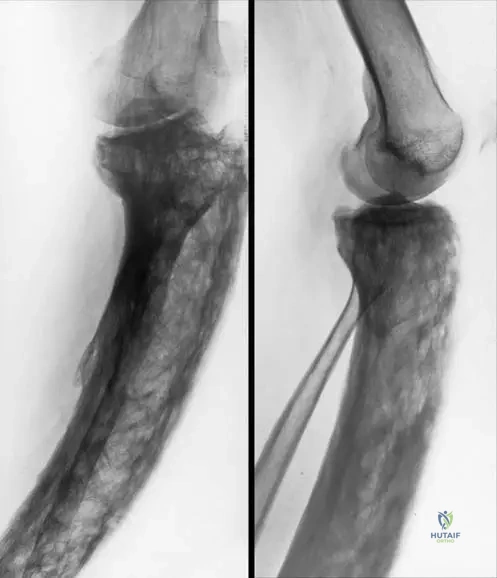

A 70-year-old male presents with isolated right femur pain and bowing, confirmed as Paget's disease. This presentation, affecting only a single bone, is referred to as:

Correct Answer: B

Rationale: The clinical context for Fig. 7.51 a, b and Fig. 7.52 a, b both refer to "Patient with monostotic Paget’s disease aff ecting the right femur" and "monostotic form" for the tibia. Monostotic refers to involvement of a single bone. Polyostotic Paget's disease involves multiple bones. The other options are incorrect terms for this specific presentation.

A 62-year-old male is diagnosed with monostotic Paget's disease affecting his right femur. Radiographs show a laterally and anteriorly bowed long bone. Histological examination of a bone biopsy from the affected area would most likely reveal which of the following?

Correct Answer: C

Rationale: The text states, "Bone changes in Paget’s disease are characterized by the development of “woven” bone and lamellar pattern of collagen." This is the hallmark histological finding. Option A is incorrect as the bone is abnormal. Option B describes osteomalacia. Options D and E are not characteristic histological features of Paget's disease.